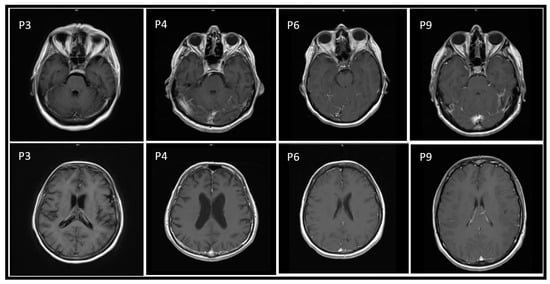

| MR | NA | Negative | Meningeal inflammation | Meningeal inflammation | Negative | Meningeal inflammation | Meningeal inflammation | Gliosis | Meningeal inflammation |

| Diagnostic follow-up | No | No | No | CT (negative) | MR (unchanged) | No | No | CT (unchanged) | MR and EEG (post inflammatory damage) |